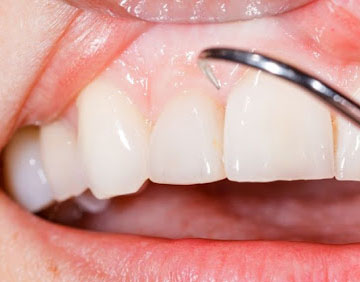

Ortodonti

Ortodontik Tedavi çapraşık, yamuk, üst üste binmiş dişlerin tedavi edilerek düzgün bir dizilim elde etme tedavisidir. Dişler ağız içinde düzgün bir dizilime kavuşturulurken ağız ve çene yapısındaki bozukluklar giderilmeye çalışılır. Üst ve alt çenenin uygun ağız kapama yapısına kavuşması için gerekli olarak yapılan tüm çalışmaları kapsar.

Ortodontik Tedavi uygulanmaması durumunda çapraşık yapıdaki dişlerin arası iyi temizlenemediği için sağlam diş zamanla çürüyecektir. Aynı zamanda diş eti (periodontal) problemleri de beraberinde görülecektir. Ağız içi hijyeni tam olarak sağlanamadığı için genç yaşta doğal dişlerin kaybı söz konusu olmaktadır. Alt ve üst çene tam kapama sağlayamadığı (maloklüzyon) için burun, geniz, sinüs ve boğaz enfeksiyonları sık olarak tekrarlanacak ve antibiyotik kullanımı artacaktır. Tüm bunların uzun vadede vücudumuza verdiği zarar yanında estetik bir gülüş de sağlanamamış olacaktır.

Ortodontik Tedavide Diş Teli (Braket) Uygulaması Nasıl Yapılır?

Braket uygulaması dişlere önden veya arkadan tel takılarak yapılır. Braketler dişler üzerine özel bir materyalle yapıştırılır. Üzerine yerleştirilen tellerle dişlere kuvvet uygulanır ve böylece dişlerin hareket etmesi ve düzgün sıralanması sağlanır. Uygulamanın amacı dişleri olmasını istediğimiz düzene sokup orada sabit kalmasını sağlamaktır. Diş tellerinden çekinen çocuklar için çeşitli renklerde veya hayvan figürleri şeklinde teller bulunmaktadır. Çocukların gözündeki ön yargıyı kırmak için bu tür uygulamalar ve diş hekiminin sıcak yaklaşımı etkili olmaktadır.